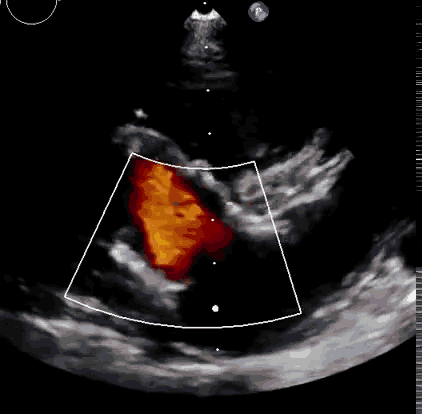

上海中山醫(yī)院葛均波院士、錢菊英院長、周達(dá)新教授、潘文志教授、潘翠珍教授、李偉教授共同完成此次臨床前研究。術(shù)后葛均波院士對(duì)Lux-Valve Plus的器械操作性能給予了高度評(píng)價(jià),DSA和超聲影像也顯示出在本次研究中Lux-Valve Plus的安全性和有效性俱佳。

本次臨床前研究經(jīng)右側(cè)頸靜脈置入LuX-Valve Plus輸送系統(tǒng)可調(diào)彎鞘管,在DSA及超聲引導(dǎo)下將人工三尖瓣瓣膜植入到原有三尖瓣位置,利用獨(dú)特的錨定技術(shù)將人工瓣膜支架可靠固定在預(yù)定的位置。